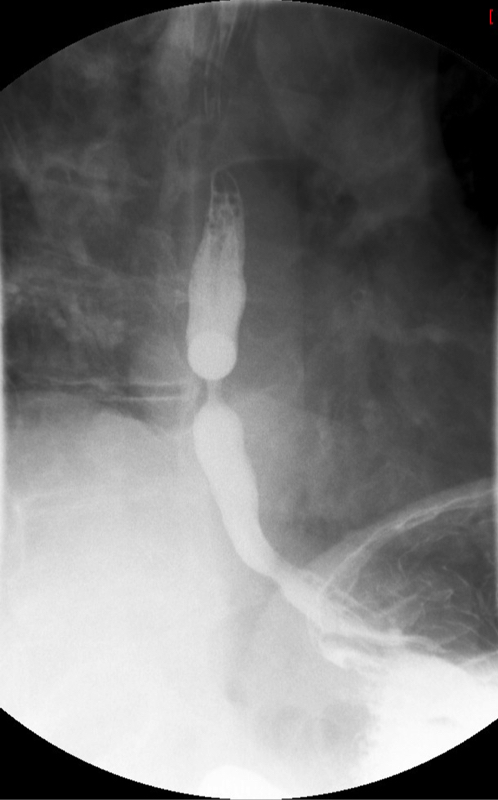

- Method—Cervical:

- Start with the patient in the upright lateral position.

- Ensure the fluoro machine is set to 4 images per second (rapid sequence).

- Explain to the patient that you are going to have them take a "comfortable mouthful" of barium and that they will need to hold it in their mouths until you count to 3.

- Make sure they understand that they are not to swallow until the count of 3.

- Once the patient has taken the "comfortable mouthful" of barium, center the fluoroscope on the cervical esophagus.

- Once the fluoroscope is properly positioned, begin counting. On the count of 2, begin taking rapid sequence images of the contrast material bolus as it moves through the cervical esophagus

(key image 1)

- Take the fluoroscope off rapid sequence.

- With the patient in the lateral position, obtain a spot film of the pharynx and cervical esophagus while they phonate the letter "e"

(key image 2).

- Cervical images are obtained in the lateral and AP projections as the patient swallows thick barium.

- Cervical image are obtained using rapid sequence fluoroscopic spot films at a rate of 4 frames per second.

- To time this appropriately, you will count to 3. You will begin to take images on 2, the patient will swallow on 3.